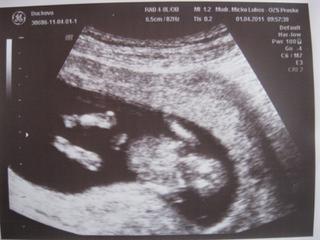

Ahojte, opäť sa ozývam po dlhšom čase 🙂 v stredu sme mali výsledky z krvi a moču, vsetko je OK. Dnes som bola na prvej poradni - dostala som tehu knižku a prenatal box 🙂)) na merania som mala ísť až bud. týždeň, ale nakoniec sme to vybavili dnes - všetko je v poriadku. Drobček je omnoho väčší ako naposledy, už sa to podobá na človiečika - krásne bolo vidno, rúčky, nožky, hlavičku, telíčko...srdiečko nám pekne pravidelne bije. Bábo si akurát žmolilo očká rúčkami, keď sme sa pozerali - úžasný pohľad 🙂 mám aj foto, neskôr pridám. Vôbec mi nebýva zle, už to asi ani nezačne, však? Doktor povedal, že mám byť len rada 🙂 držkajte sa, pekný dník a víkend.